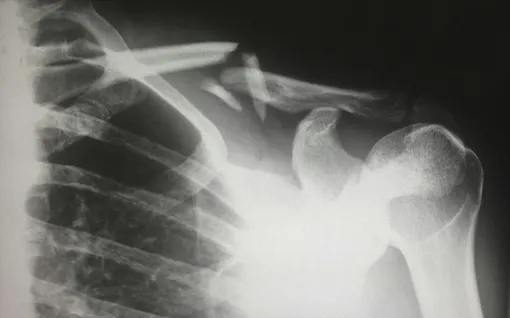

Создатели Bone-02 приводят в качестве примера реальный клинический случай с пациентом, который обратился за помощью к медикам после того, как сломал запястье. Ученые сделали на его руке разрез длиной около 3 сантиметров и ввели туда порцию Bone-02. Как утверждают авторы разработки, перелом «зажил» буквально на глазах – для этого понадобилось лишь три минуты. При этом полноценная операция по восстановлению работоспособности запястья потребовала бы установки металлической пластины и винтов, для удаления которых хирургам пришлось бы провести пострадавшему повторную операцию примерно через год.

Врачи отслеживали состояние здоровья пациента с «заклеенным» запястьем на протяжении около трех месяцев. Наблюдения показали, что его перелом сросся полностью и без осложнений.